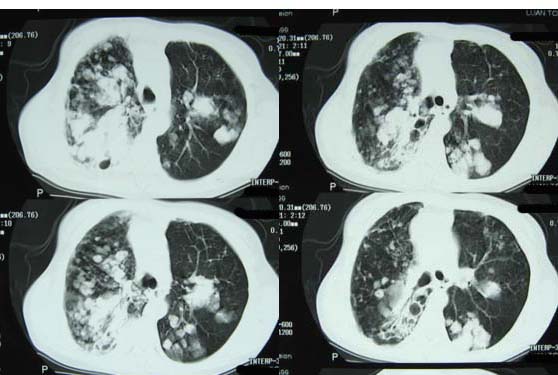

标题: CT8382:男,75,咳嗽,咳血有半年时间。 [打印本页]

标题: CT8382:男,75,咳嗽,咳血有半年时间。

右肺下叶弥漫性片状增高影 纤维组织增生   左肺上叶尖段大结节样增高影边界清楚 中叶下叶大片增高影(内可见钙化)

1.吸入性肺炎(真菌性)

2.干酪型肺炎

3.继发性肺结核?